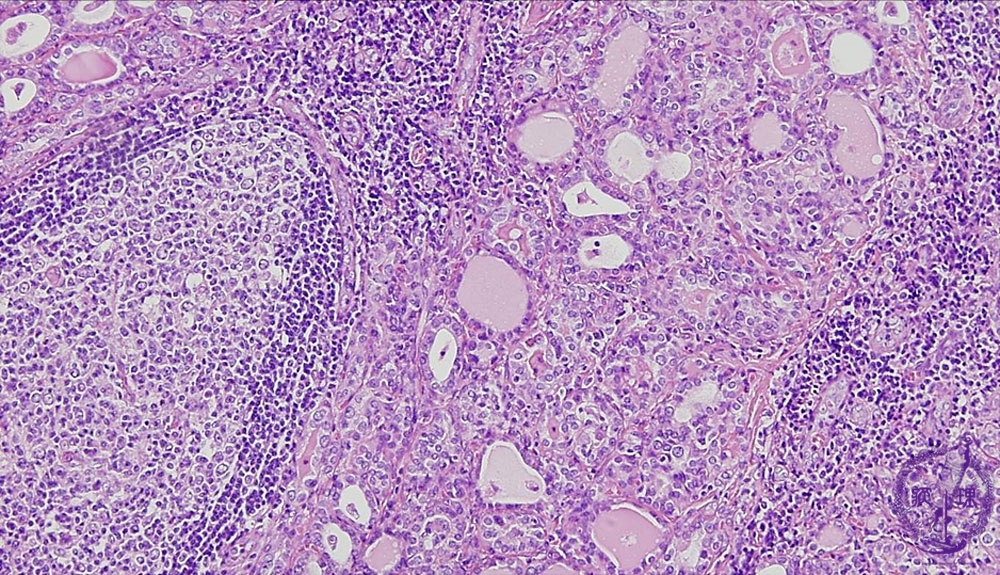

- ★(4)Chronic thyroiditis (Hashimoto disease)

Microscopic findings (HE stain, middle power view). Marked lymphocytic infiltrations, lymphoid follicles, atrophic thyroid follicles (dotted -line) with associated decreases of colloid material, are detected.